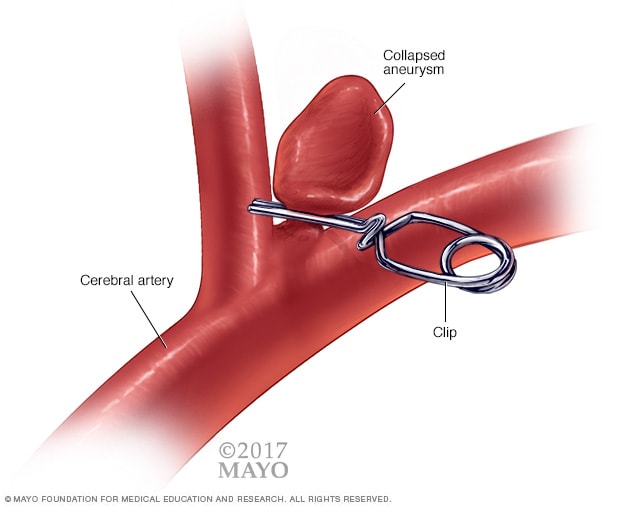

Снимки и иллюстрации микроаневризм сосудов головного мозга